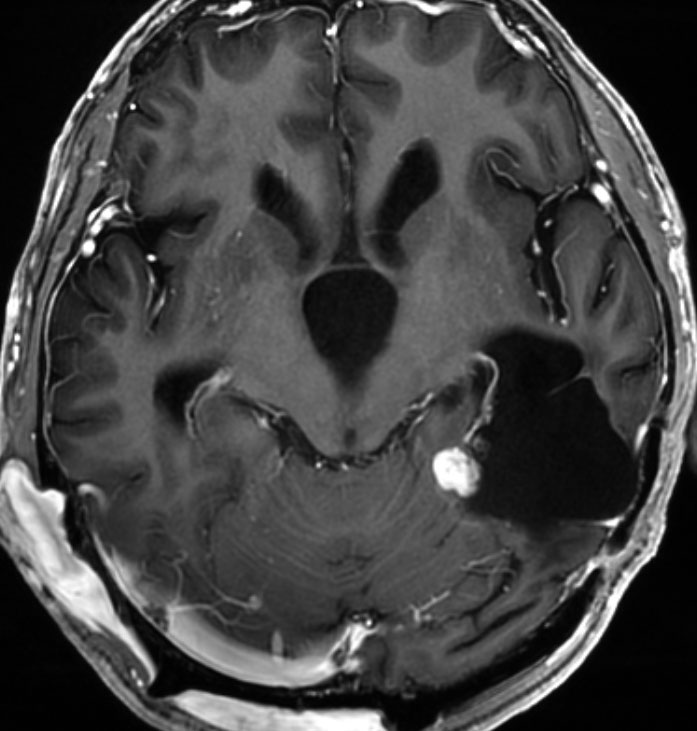

12歳時,私のところへ来た時のガドリニウム増強像です。開頭手術で扁桃体を含めて全摘出してから発作は止まり,術後3年で抗てんかん薬は中断できています。

- MRIでは大脳表面にあり,のう胞(液体の溜まっている袋)と腫瘍の塊があります

- 大脳にくっついているのですが,大脳の中には育たないで,大脳からキノコのように生えてこともあります

- 大脳表面ののう胞を伴う限局性の腫瘍で,原則的にはくも膜下腫瘍ですが硬膜にも付着することが多いです

- 側頭葉表面に頻度が高いです,次いで前頭葉です